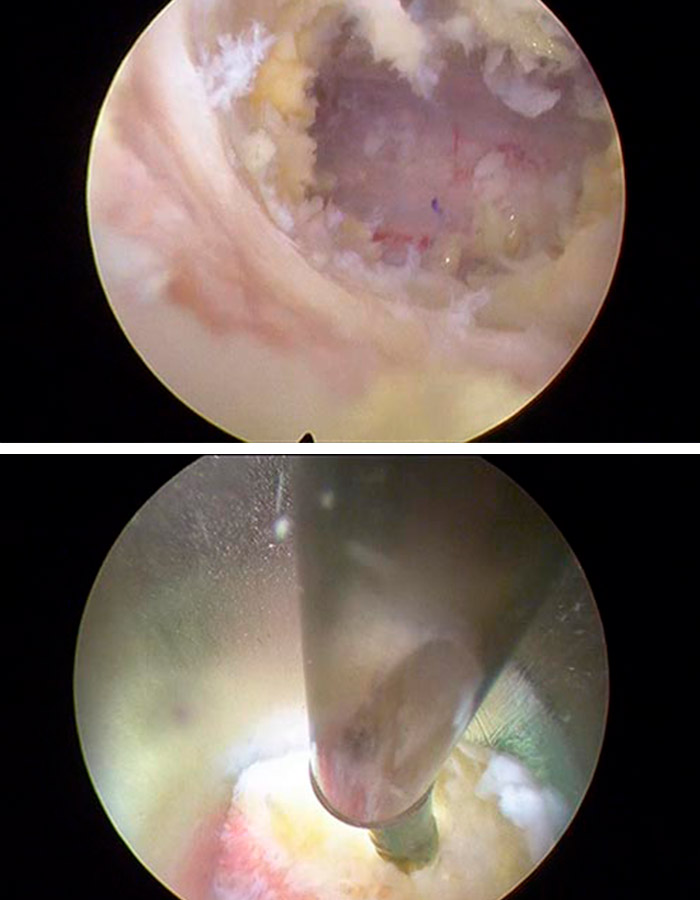

Para poder dar un diagnóstico observamos durante 6 meses la evolución de la paciente en el marco, y sobre la hernia foraminal L5-S1 y localizamos el problema. Presentaba una estenosis de canal entre las vértebras L4-L5 tal y como se puede ver en las siguientes imágenes.

Liberacion de estenosis de canal

Para poder efectuar la operación, realizamos un abordaje inter-laminar posterior con una aguja guía y dentro un dilatador que nos permite no dañar ningún tejido neurológico, muscular u óseo y acceder directamente a la zona en la que vamos a trabajar.

Procedemos a la liberar de la estenosis el canal con mucha delicadeza y revisando que no quede ningún resto, todo ello mediante una incisión cutánea de 3mm muy precisa.

Tras realizar este vaciado comprobamos cómo queda adecuadamente liberadas las estructuras neurológicas vigilando que el espacio que queda ahora sea el correcto.